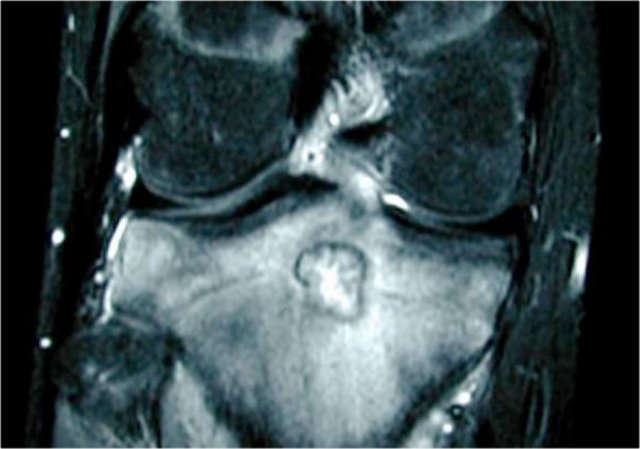

On the left more examples of GCT around the knee.

Notice that most of these lesions are well-defined and located in the epiphysis and extend into the metaphysis.

Some extend onto the articular surface (yellow arrow and small red arrows).

The lesion on the upper right has an ill-defined border with a broad zone of transition (blue arrow).